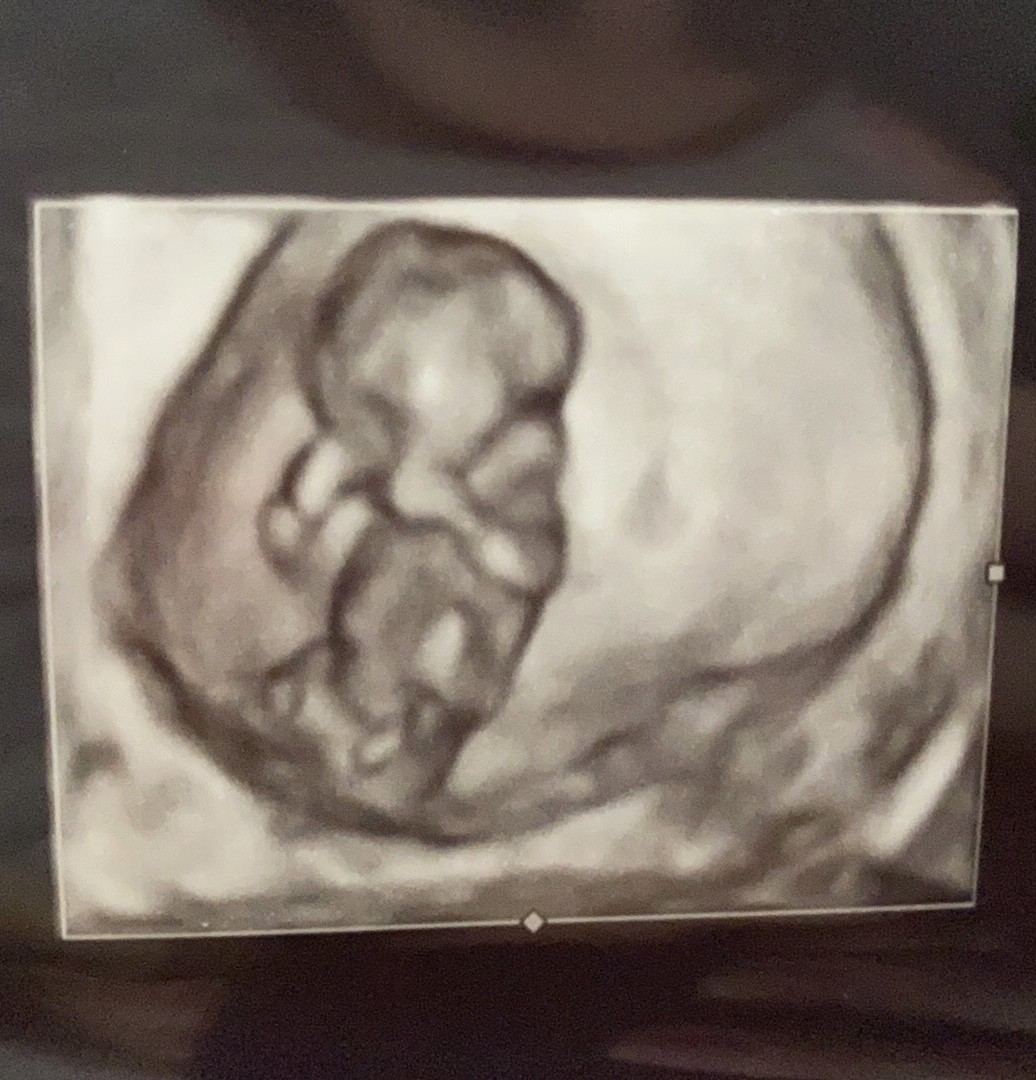

Juz nie mogę sie doczekać, od lekarza jeszcze nic nie usłyszałam ale jestem ciekawa czy wy cos widzicie

nie widzę wyrostka płciowego. może któraś dojrzy, ale ja tu nie widzę. po wyrostku da się dojrzeć płeć, u mnie się sprawdziłood tak zwykle pytanie, moze ktoś cos zauważy, po co ta uszczypliwość![]()